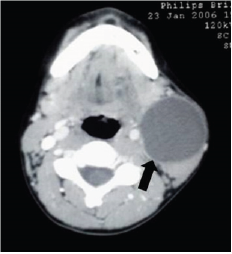

BCAs are the second most common CNL and comprise 20%-30% of all head and neck lesions [21,25-27]. It is reported that there is an equal sex distribution in BCAs [25,28]. Although branchial remnants are relatively rare, which can present in a variety of ways depending on the origin of the cleft, the most common type is the second cleft anomalies accounting for 95% of all lesions [1,5]. In classic cases, complete history and physical examination is adequate for diagnosis and no additional evaluation may be necessary (Figure 2). An upper airway endoscopy may be useful in determining the presence of a pharyngeal opening [21]. On the contrary to adults, FNA should not be performed and incisional biopsy should be avoided in children otherwise resection of branchial lesion will be technically more difficult [25]. US and CT may be helpful in defining the lesion and its anatomic course (Figure 3). These imaging modalities should be performed preoperatively for complete visualization of the tract [25]. Common current practice is to obtain a preoperative US for planning the treatment.

Figure 3: Axial CT image in a child with a second branchial cleft cyst (Arrow: cystic mass).